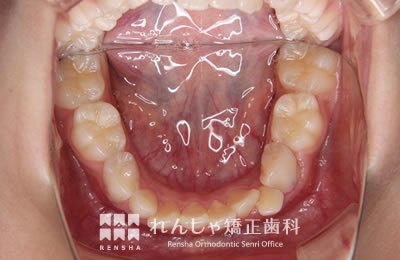

中高生

永久歯列はほぼ完成してしますが、歯列を側方だけでなく後方へも拡大し、埋まっていた右上奥歯を引っ張り出しています。

| 主訴 | 埋まったままでてこない歯がある |

|---|---|

| 診断名 | Angle Class II 小臼歯の埋伏と叢生を伴う上顎前突 |

| 初診時年齢 | 13歳5か月 |

| 装置名 | マルチブラケット装置 |

| 抜歯非抜歯 | 非抜歯 |

| 治療期間 | 2年3か月 |

| 費用の目安 | 約82万円+消費税(検査料金、都度の処置費用等も合わせた総額) |

| リスク副作用 | 歯の移動に伴う軽微な歯根吸収、歯槽骨吸収、歯肉退縮(本症例では軽度の歯根吸収を認めた)、矯正器具装着中のカリエスリスク増大(本症例ではカリエス発生無し) |